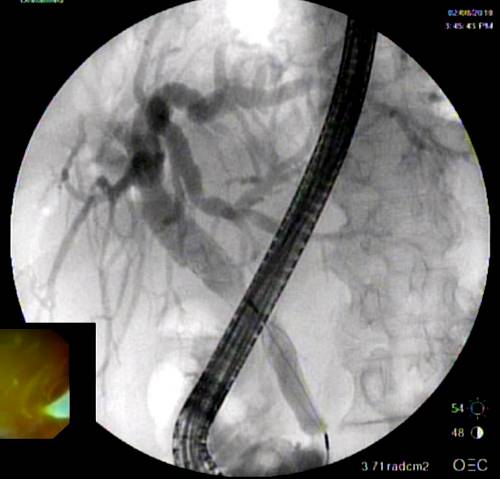

Представлены клинические наблюдения редкого осложнения эхинококкоза печени – прорыва эхинококковой кисты в желчные протоки. Осложнение стало причиной обструкции желчных протоков, механической желтухи и холангита. Освещены этапы диагностики, роль УЗИ в выявлении осложнений эхинококкоза печени, рассмотрены способы минимально инвазивного лечения с применением эндоскопических и чрескожных технологий под контролем лучевых методов.